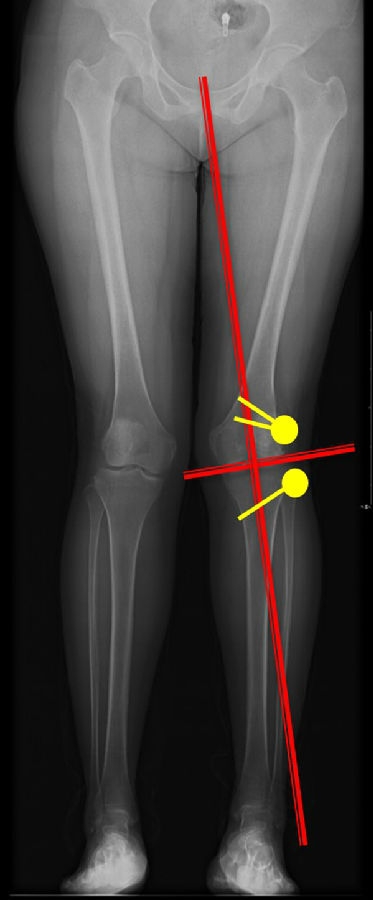

以两例病例展示术前设计的五步。患者一,女性,42岁,左膝疼痛2年,加重1年。

步骤一:判断内外翻畸形

画下肢机械轴,股骨头中心链接踝关节中心判断患者为内翻畸形还是外翻畸形。此患者为外翻畸形。

步骤二:判断畸形部位

量股骨远端外侧角和胫骨近端内侧角,判断畸形在股骨、胫骨还是关节内。此患者股骨侧有畸形,LDFA=76°,MPTA=81°,无关节内畸形。

步骤三:设定目标力线

以关节线为基准参考线,设定目标力线与关节线垂直。

步骤四:确定合页位置和截骨线方向

此患者计划股骨内侧闭合楔,胫骨内侧开放楔。

步骤五:Miniaci法测量角度

以股骨侧合页为旋转中心,以股骨头中心到合页的距离为半径,进行旋转,直到该线段与目标力线相重合,此时重合角度即为股骨需要闭合的角度,同时胫骨侧也能计算出开放的角度。此患者需要股骨闭合14°,胫骨开放8°。